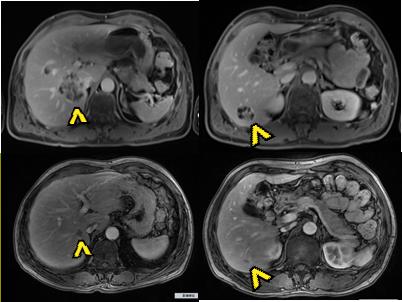

2019年10月至2020年2月:吉西他滨+顺铂 + PD-1*制剂抑** /Q21d,5周期,中间复查MRI示:病灶明显缩小。疗效评价PR。

MRI示:免疫联合化疗后,病灶明显缩小。上图:治疗前;下图:治疗后